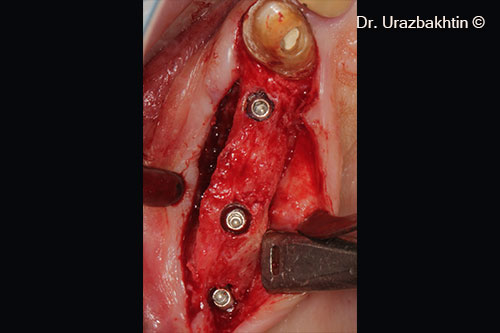

Installation of Astra Tech TX dental implants